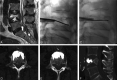

Fig 4.

A, A 71-year-old woman with undifferentiated cancer and a lesion at L4. B and C, A void is created in the vertebral body by debulking the spinal tumor using the plasma radio-frequency–based wand before vertebral body augmentation with bone cement. D–F, Axial (D and E) and sagittal (F) views by using MR imaging show excellent anterior placement of bone cement.